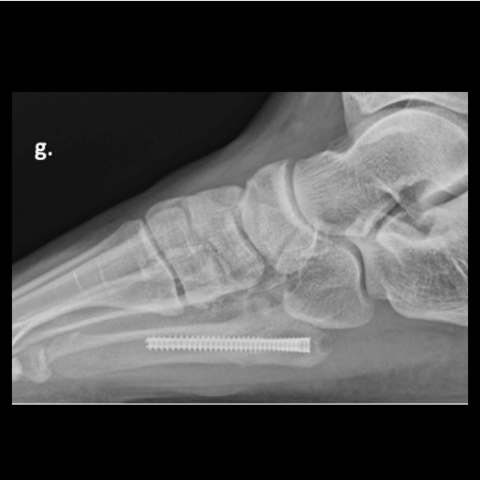

Figure 2g

Figure 2g. Here is the 30-year-old soldier’s foot 3 months post-injury.